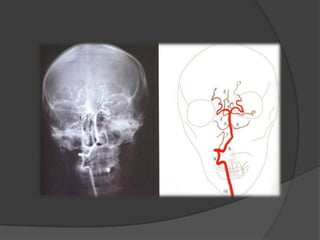

Estudio de vascularización de sistema nervioso

central y de sus alteraciones mediante la inyección

arterial de un medio de contraste radiopaco y la

obtención de diversas proyecciones con rayos X.

Angiografía convencional

   La angiografía es un examen de diagnóstico

por imagen cuya función es el estudio de los

vasos circulatorios que no son visibles

mediante la radiografía convencional.

CAYADO AÓRTICO